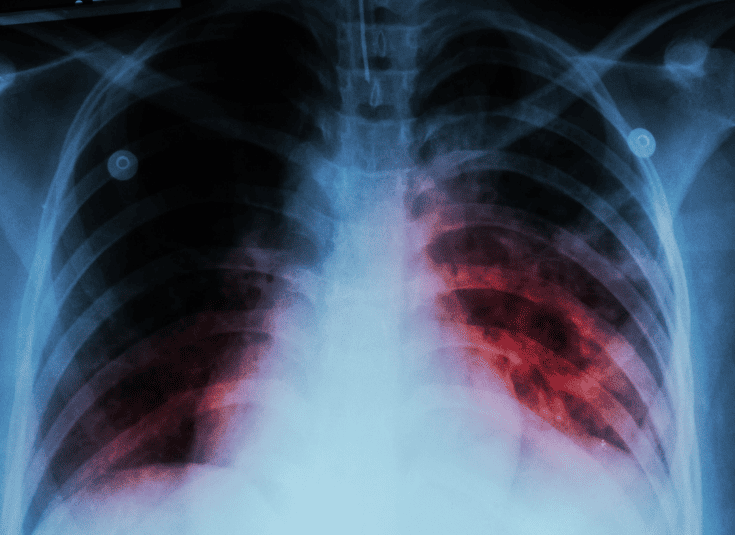

Tuberculosis (TB) is a serious infectious disease primarily affecting the lungs but can spread to other parts of the body. Caused by the bacterium Mycobacterium tuberculosis, TB is transmitted through the air when an infected person coughs or sneezes. Symptoms typically include a persistent cough, chest pain, fatigue, and night sweats. As an experienced infectious disease specialist, Dr. Ankita Baidya offers accurate diagnosis and treatment for TB. Early detection and treatment are critical in preventing complications and the spread of TB to others. Dr. Baidya ensures that every patient receives comprehensive care tailored to their needs.

The treatment of tuberculosis requires a combination of antibiotics taken over an extended period, usually 6-9 months. Dr. Ankita Baidya focuses on providing personalized treatment plans based on the type of TB and individual patient health conditions. For drug-resistant tuberculosis (MDR-TB), specialized medications and a more rigorous treatment approach are necessary. Dr. Baidya emphasizes the importance of medication adherence to ensure the success of the treatment and avoid resistance. Alongside medication, she provides supportive therapies to help patients manage symptoms and improve their overall health throughout the treatment process.